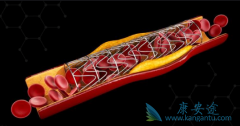

心脏支架作为现代心血管医学发展中的一个里程碑,确实在冠心病的治疗中发挥着非常重要的价值。 生物可降解支架 给冠心病介入治疗带来了新的革命。但是生物可降解支架真的能成为心血管患者的福音吗?目前心脏支架主要分为不可降解支架和完全降解支架两个 ...

生物可降解支架 安全吗?其实早在20世纪90年代初,就已经提出生物可降解支架的概念,但发展没有金属裸支架和药物洗脱支架快,最终被药物洗脱支架所替代。目前药物洗脱支架长期随访发现潜在的支架内血栓风险,最近10余年生物可降解支架科技和材料学取得 ...

为了改善冠心病介入治疗短期和长期的疗效与安全性,所以研发了支架。第一代支架是金属裸支架,使冠心病介入治疗前进了一大步,使介入治疗变得非常安全,当血管发生严重狭窄时单纯球囊扩张预处理后,再用支架把血管完全撑开,就能解除心肌缺血危险,而且 ...